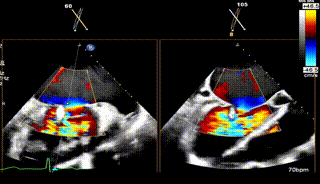

术前TEE评估

术前瓣膜介入团队的心超医生陈星星医师王良国医师对患者的心脏结构和瓣膜解剖情况进行详细的评估:

1.二尖瓣重度关闭不全(4+),瓣环明显扩大(AP径4.6cm,LM径3.9cm),扁平,关闭时瓣叶对合不佳(carpentier I),1-3区均可见反流束,返流宽度达26mm;肺静脉频谱呈收缩期反向。

2.画迹法测得二尖瓣瓣口面积约8.8cm²。

3.PISA法测得EROA=0.57cm²,Rvol=77ml,r=11mm。

4.二尖瓣前叶(A2)长度29mm,后叶(P2)长度11mm。

5.左房巨大(三径86*84*114mm),右房巨大(内径114*86mm),CFI提示极重度三尖瓣反流,Teich法测得EF为70.1%。

3区

3区带彩

3D

3D带彩